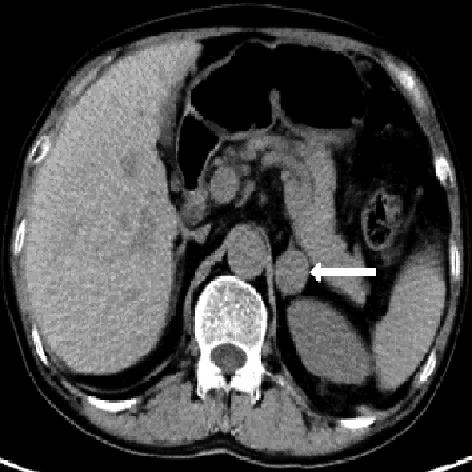

• 嗜铬细胞瘤及副神经节瘤不同生化表型的CT征象对比研究

2024, 49(2):203-209. DOI: 10.13406/j.cnki.cyxb.003433

摘要 (51) HTML (33) PDF 3.10 M (96) 评论 (0) 收藏

摘要:目的 分析生化阴性嗜铬细胞瘤及副神经节瘤(pheochromocytomas and paragangliomas,PPGLs)的电子计算机断层扫描(computed tomography,CT)征象是否有别于生化阳性PPGLs,同时了解生化阳性PPGLs不同表型的CT征象是否存在差异。方法 回顾性分析131例PPGLs患者的术前腹部增强CT图像,包括肿瘤位置、大小、形态、囊变坏死、液-液分层、钙化、向心结节状强化、肿瘤内粗大血管、强化包膜、绝对廓清率及相对廓清率。根据生化水平,将患者分为生化阳性组和阴性组,阳性组进一步分为去甲肾上腺素型、肾上腺素型及多巴胺型。比较各组及各表型间的CT征象差异。结果 相较于生化阴性组,阳性组PPGLs更大(Z=-2.064,P=0.039)、囊变坏死(χ2=6.610,P=0.010)及向心结节状强化(χ2=3.909,P=0.048)的比例更高;相较于去甲肾上腺素型,肾上腺素型PPGLs更大(Z=-2.036,P=0.042)、强化包膜比例更高(χ2=7.242,P=0.007)。结论 肿瘤大小、囊变坏死及向心结节状强化的CT征象有助于术前诊断生化阴性PPGLs,肿瘤大小及强化包膜有助于解释去甲肾上腺素型及肾上腺素型PPGLs不同临床表现产生的机制。